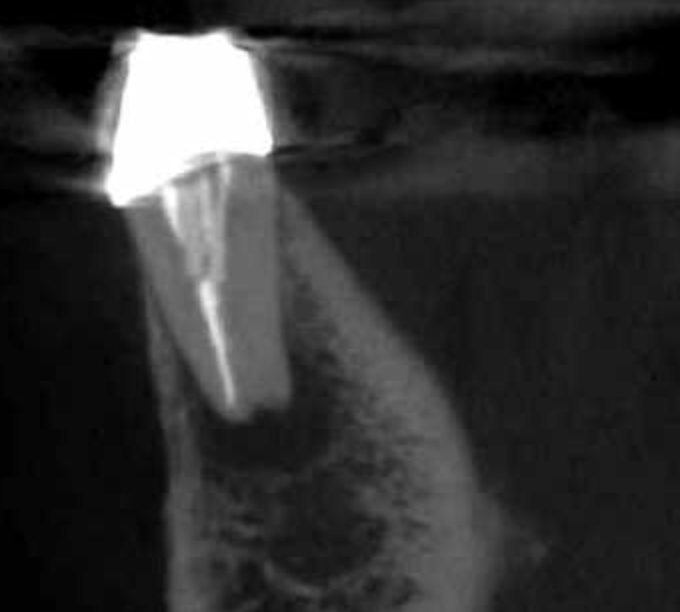

Vertical root fracture